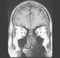

MRI of the eyeball and optic nerve CT of the eyeball and optic nerve MRI of eye muscles Review the actions of the extraocular muscles from an anterior view of the bulb.